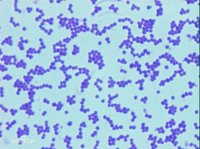

球菌是細菌中的一大類。對人類有致病性的病原性球菌(Pathogeniccoccus)主要引起化膿性炎症,所以稱為化膿性球菌(Pyogeniccoccus),其中革蘭氏陽性菌主要包括葡萄球菌、鏈球菌、肺炎球菌;革蘭氏陰性菌包括腦膜炎球菌和淋球菌等。